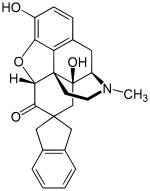

The pharmacodynamic response to an opioid depends upon the receptor to which it binds, its affinity for that receptor, and whether the opioid is an agonist or an antagonist. For example, the supraspinal analgesic properties of the opioid agonist morphine are mediated by activation of the μ1 receptor; respiratory depression and physical dependence by the μ2 receptor; and sedation and spinal analgesia by the κ receptor. Each group of opioid receptors elicits a distinct set of neurological responses, with the receptor subtypes (such as μ1 and μ2 for example) providing even more [measurably] specific responses. Unique to each opioid is its distinct binding affinity to the various classes of opioid receptors (e.g. the μ, κ, and δ opioid receptors are activated at different magnitudes according to the specific receptor binding affinities of the opioid). For example, the opiate alkaloid morphine exhibits high-affinity binding to the μ-opioid receptor, while ketazocine exhibits high affinity to ĸ receptors. It is this combinatorial mechanism that allows for such a wide class of opioids and molecular designs to exist, each with its own unique effect profile. Their individual molecular structure is also responsible for their different duration of action, whereby metabolic breakdown (such as N-dealkylation) is responsible for opioid metabolism.

Several semi-synthetic opioids were developed in Germany in the 1910s. The first, oxymorphone, was synthesized from thebaine, an opioid alkaloid in opium poppies, in 1914.[228] Next, Martin Freund and Edmund Speyer developed oxycodone, also from thebaine, at the University of Frankfurt in 1916.[229] In 1920, hydrocodone was prepared by Carl Mannich and Helene Löwenheim, deriving it from codeine. In 1924, hydromorphone was synthesized by adding hydrogen to morphine. Etorphine was synthesized in 1960, from the oripavine in opium poppy straw. Buprenorphine was discovered in 1972.[228]

- Buprenorphine